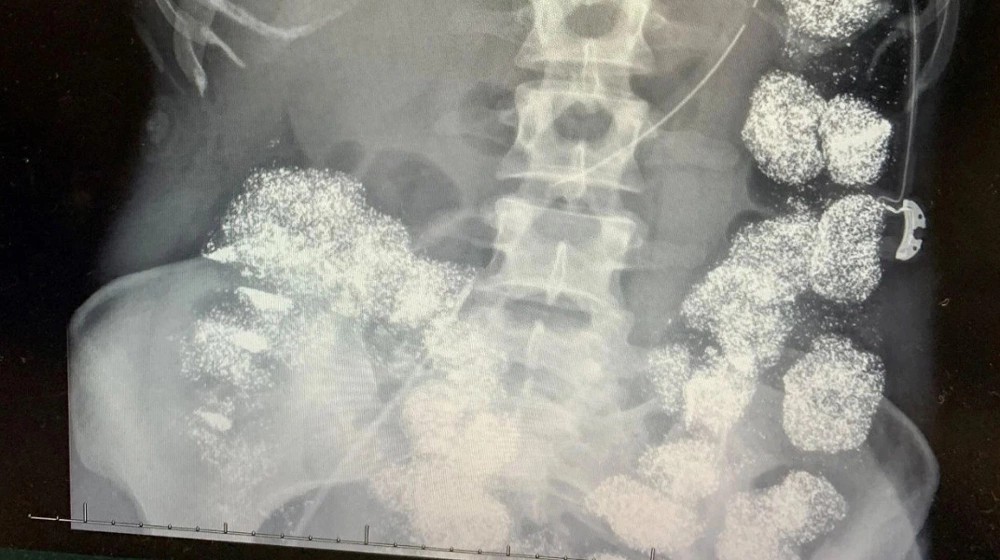

Mọi nghi ngờ bùng nổ khi xét nghiệm máu cho thấy nồng độ chì trong cơ thể Hannah vượt quá 80 mcg/dL, cao gấp 8 lần ngưỡng an toàn. Chụp X-quang phát hiện kim loại nặng phủ kín dạ dày, đại tràng và đã ngấm vào xương.

Các bác sĩ khẳng định: không có cách nào để một người vô tình nuốt lượng chì khổng lồ như vậy. Bệnh viện lập tức báo cảnh sát, mở cuộc điều tra với những người thân cận nhất của nạn nhân.

Hình ảnh X-quang cho thấy cơ thể Hannah Pettey bị lấp đầy bởi chì. Ảnh: Hartselle Police Department